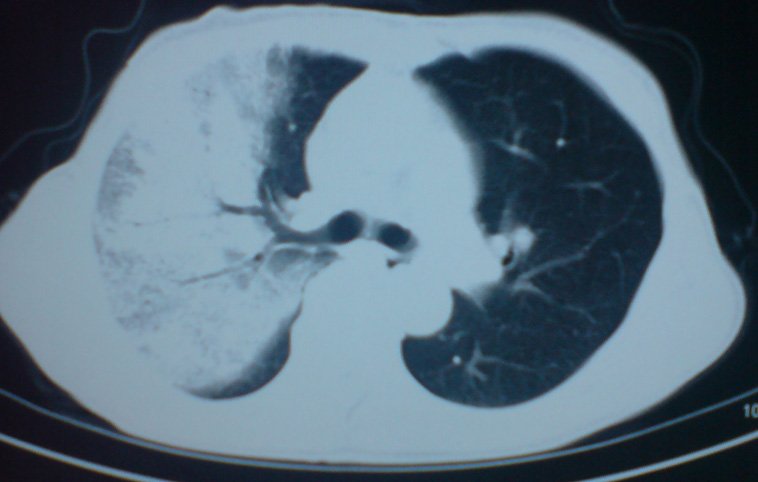

患者,女,60岁,右侧胸痛、咳嗽两个月。

首先考虑肺泡癌。

大叶肺炎,治疗后复查。

典型的细支气管肺泡癌

干酪样肺炎?肺泡癌?请结合病史,有无发热、咳痰。

应首先考虑常规病变:大叶性肺炎,抗炎治疗后复查。补充病史及发全图像看看纵膈里面有无肿大的淋巴结。

不出意外的话应该是弥漫性肺泡癌。

肺泡癌?肺泡蛋白沉积症?

考虑大叶性肺炎,抗炎治疗后复查或痰检除外肺泡癌。

支持:大叶性肺炎,病灶内支气管走行自然,无僵直及粗细改变,建议抗炎治疗后复查!